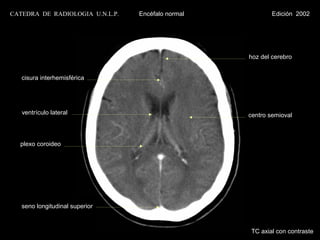

cisura interhemisférica

lóbulo frontal

cisura de Silvio

ínsula

hipotálamo

plexo coroideo                                 cisterna interpeduncular

pedúnculo cerebral

asta temporal

IV ventrículo                                  tubérculo cuadrigémino

cerebelo                                       vermis cerebeloso

lóbulo occipital

TC axial con contraste